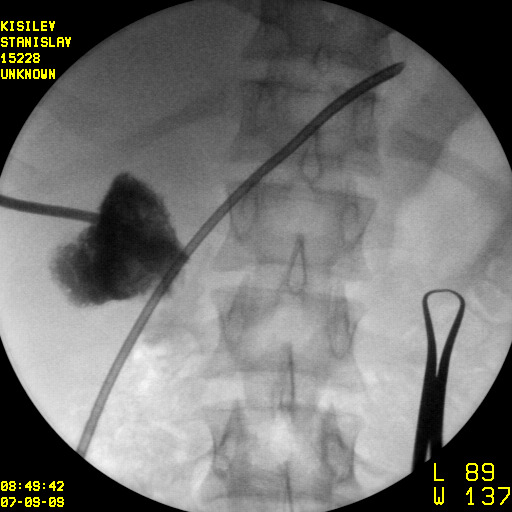

Минимально инвазивное лечение при эхинококковых кистах печени, осложнившихся прорывом в желчные протоки

Представлены клинические наблюдения редкого осложнения эхинококкоза печени – прорыва эхинококковой кисты в желчные протоки. Осложнение стало причиной обструкции желчных протоков, механической желтухи и холангита. Освещены этапы диагностики, роль УЗИ в выявлении осложнений эхинококкоза печени, рассмотрены способы минимально инвазивного лечения с применением эндоскопических и чрескожных технологий под контролем лучевых методов.